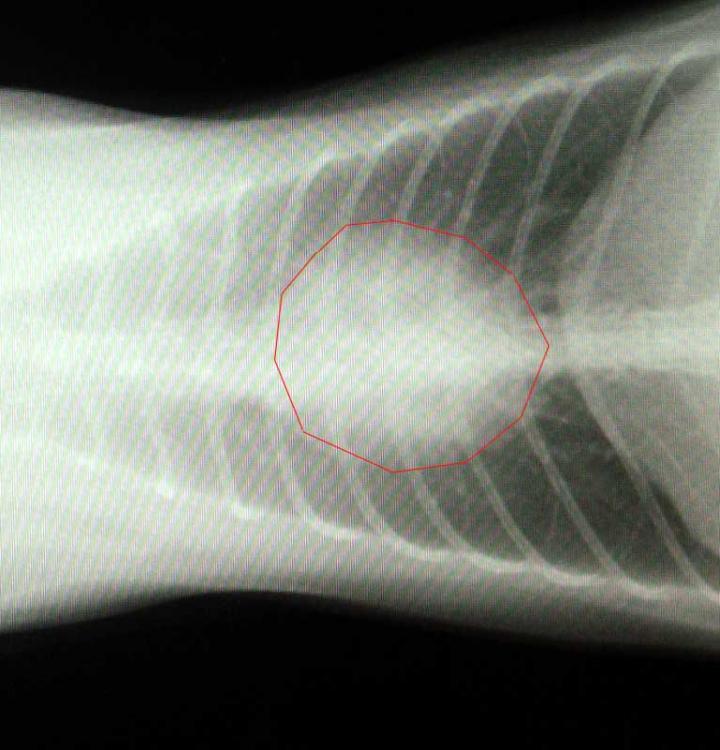

心臓の拡大です。

形が丸くなってハート型じゃなくなってます(^O^)

超音波で心筋の厚さとかを計測した結果、正常値で異常なし!